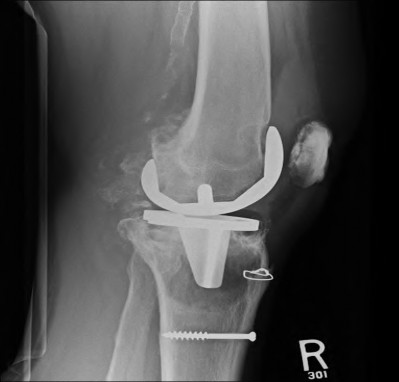

A 65-year-old woman with painful knee arthritis and the deformity seen in Figure A, is scheduled to undergo a total knee arthroplasty. All the following are risk factors for a post-operative peroneal palsy EXCEPT:

Figure A demonstrates and AP radiograph of the knee showing end-stage arthritis with severe lateral compartment narrowing.